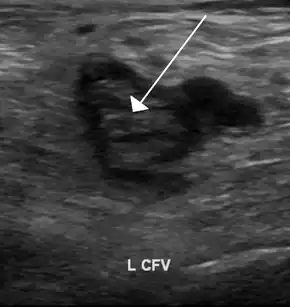

Compression ultrasonography for suspected deep vein thrombosis is the standard diagnostic method, and it is highly sensitive for detecting an initial DVT.[118] A compression ultrasound is considered positive when the vein walls of normally compressible veins do not collapse under gentle pressure.[39] Clot visualization is sometimes possible, but is not required.[119] Three compression ultrasound scanning techniques can be used, with two of the three methods requiring a second ultrasound some days later to rule out the diagnosis.[118] Whole-leg ultrasound is the option that does not require a repeat ultrasound,[118] but proximal compression ultrasound is frequently used because distal DVT is only rarely clinically significant.[117] Ultrasound methods including duplex and color flow Doppler can be used to further characterize the clot[117] and Doppler ultrasound is especially helpful in the non-compressible iliac veins.[119]

CT scan venography, MRI venography, or a non-contrast MRI are also diagnostic possibilities.[120] The gold standard for judging imaging methods is contrast venography, which involves injecting a peripheral vein of the affected limb with a contrast agent and taking X-rays, to reveal whether the venous supply has been obstructed. Because of its cost, invasiveness, availability, and other limitations, this test is rarely performed.[39]